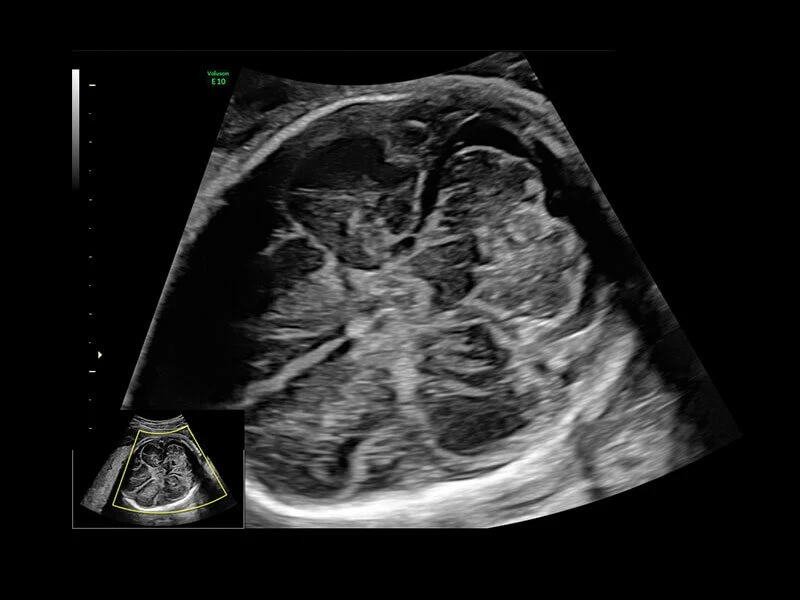

Voluson E10 – премиум класс среди ультразвуковых диагностических аппаратов для акушерских, гинекологических и объемных исследований. Аналогов системе Voluson E10 на рынке не представлено. УЗИ аппарат Voluson E10 обладает возможностью подключения электронного матричного датчика с количеством элементов не менее 8000.

Ультразвуковой аппарат идеально подходит для акушерско- гинекологических исследований. Гарантирует точное и четкое изображение.

Система обеспечивает инновационную четкость при работе. Новая платформа Radiance System Architecture системы разработана для превосходной визуализации как в стандартных режимах, так и при 3D/4D-визуализации.

Четкие и подробные изображения

В медицинском учреждении, которое работает в условиях высокой нагрузки, значение имеет каждая минута. У врача нет времени подолгу корректировать параметры настройки, чтобы добиться наилучшей детализации изображения. Инновационная архитектура УЗИ аппарата Voluson E10 избавляет вас от лишних хлопот, — вы сразу получаете безукоризненную картинку. Вам не придется тратить лишнее время и силы: качество визуализации безупречно в любом режиме — от двумерных изображений до новейших 3D/4D технологий.

Современные клинические приложения и высокое качество изображений позволяют использовать Voluson E10 для наблюдения за ходом беременности максимально эффективно. С помощью этого аппарата можно проводить любые исследования, как рутинные, так и комплексные, выявляя проблемы на ранних стадиях и принимая своевременные меры.